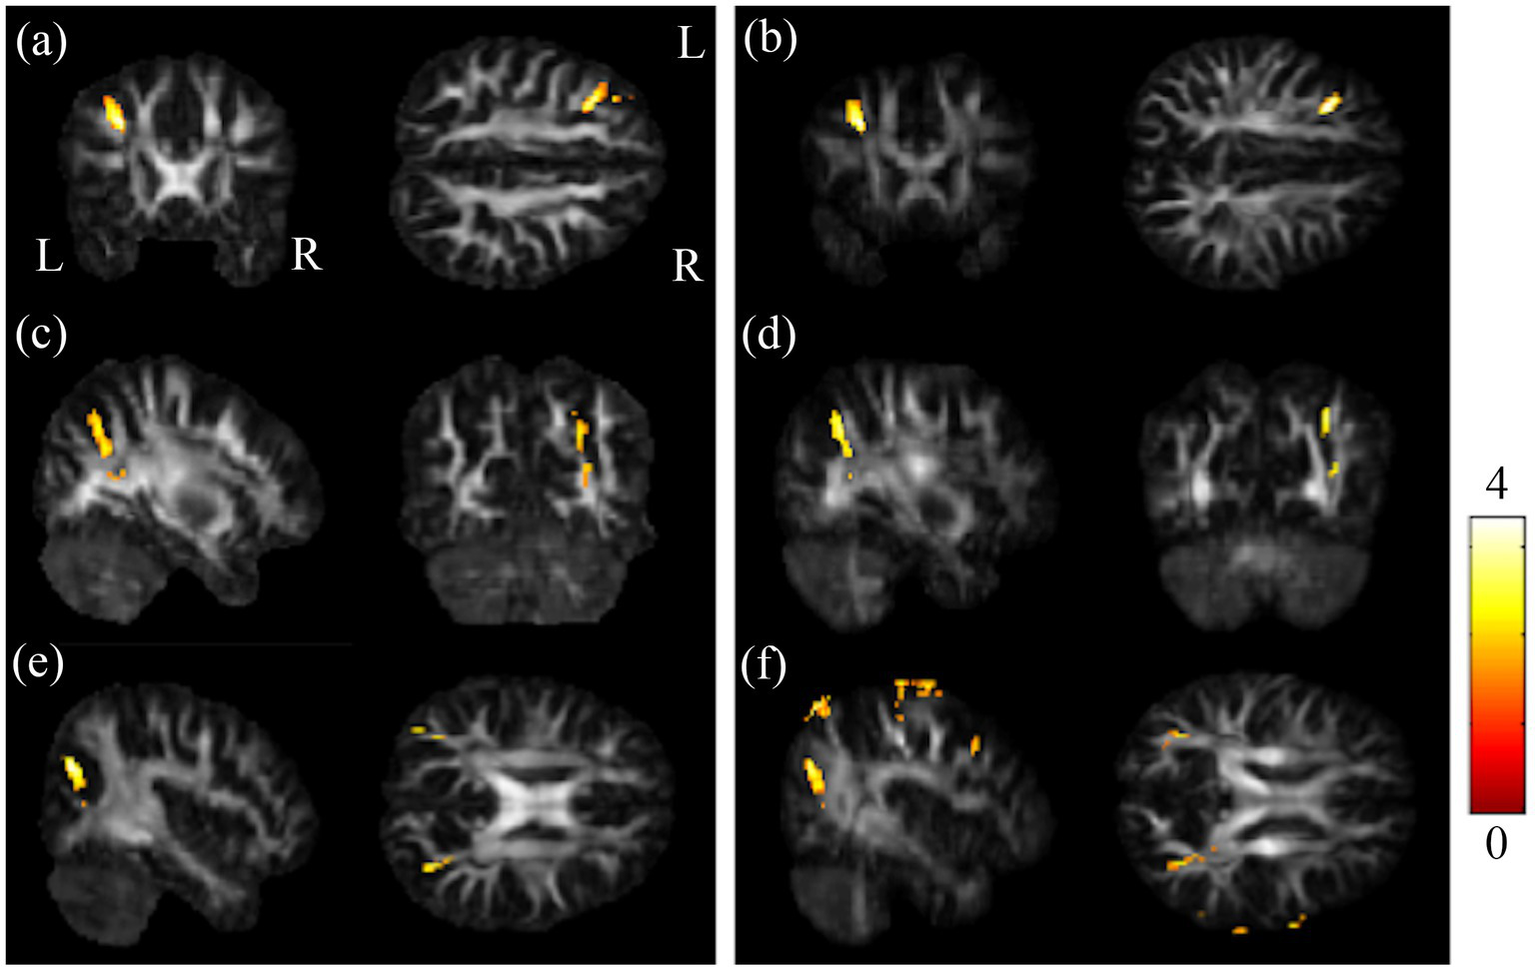

The post-hoc t-test revealed that in the group of BB, both GFA and NQA notably decreased in left MFG, right SPG, and bilateral MOG compared to HC (Figure 2). The GFA of the post-chemotherapy group were significantly lower in the CC and left MFG than HC (Figures 3A,B), and remarkably lower in left PCG and left MFG than the pre-chemotherapy group (Figures 3C,D). All the results above were listed in Supplementary Table S1.

Results of post-hoc t-test between BB and HC groups. Regions showing remarkably reduced GFA/NQA values in pre-chemotherapy patients in (A,B) l-MFG, (C,D) r-SPG, and (E,F) bi-MOG. The left column was the results of GFA. And the right column was the results of NQA (α = 0.05). The color bar represents t-scores of t-statistics. Please look for the abbreviation details in the Appendix.

Figure 3

Results of post-hoc t-test showed HC and BB groups larger than BA group. Results of this study demonstrated that the chemotherapy-treated group had significant lower GFA values in (A) CC as well as (B) l-MFG compared to HC, and reduced GFA values in (C) l-PCG as well as (D) l-MFG compared to BB (α = 0.05). The color bar represents t-scores of t-statistics. Please look for the abbreviation details in the Appendix.